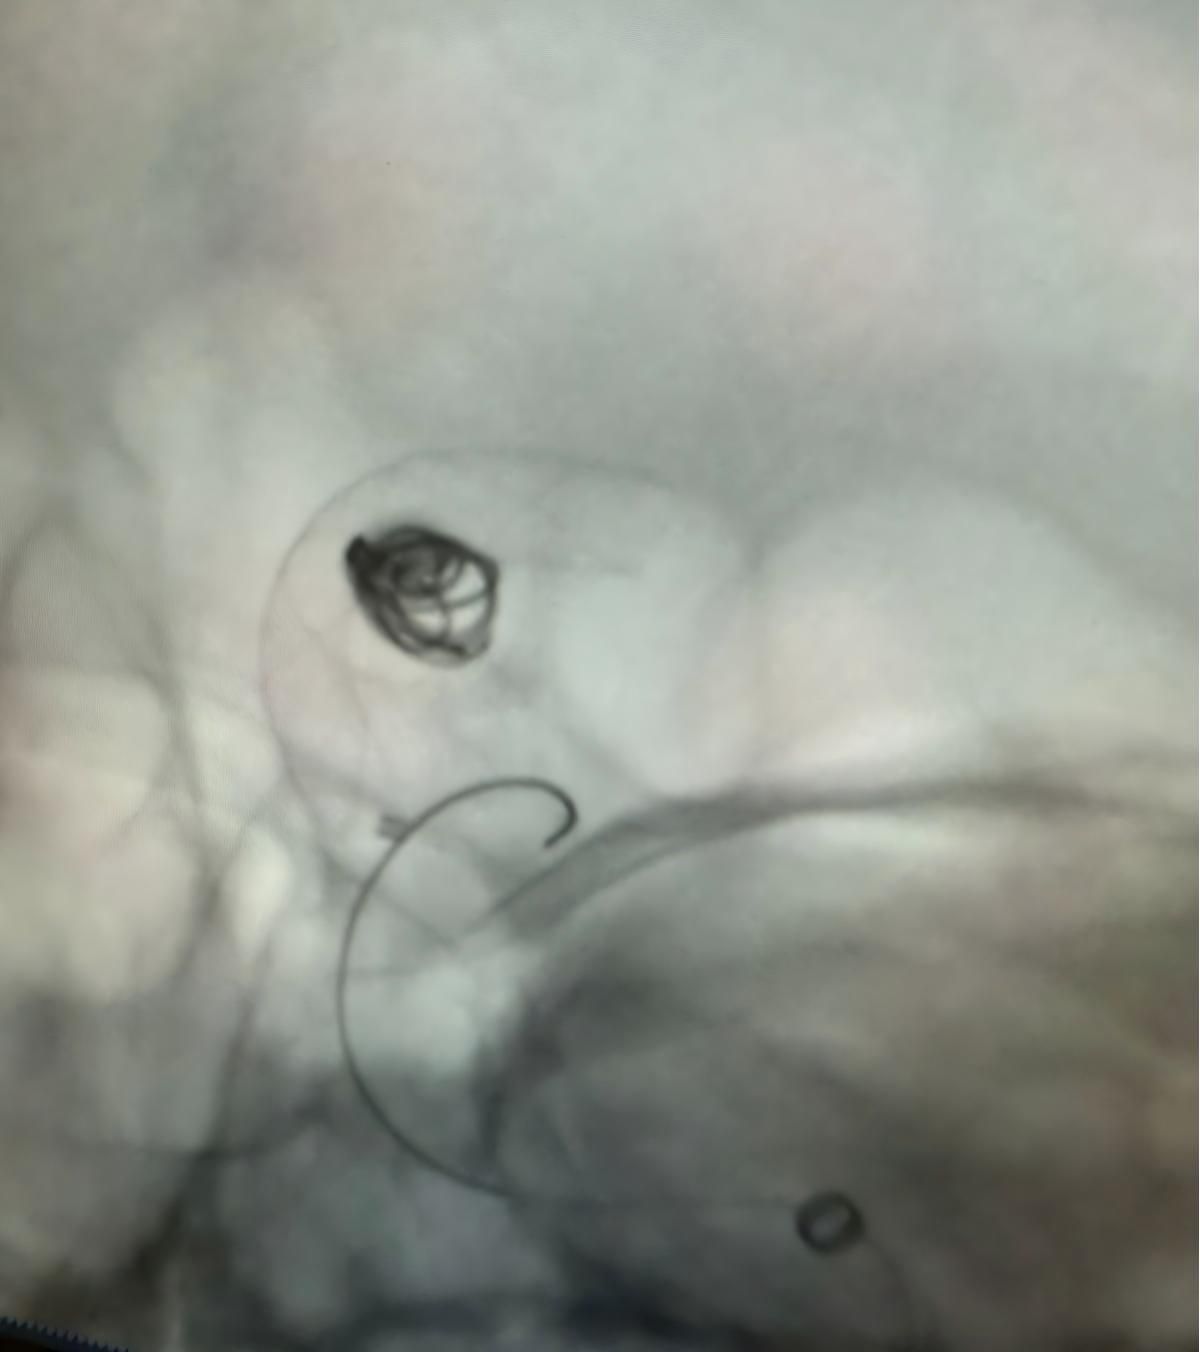

Temos o prazer de compartilhar um recente procedimento bem sucedido na Clínica Alma Mater, Medellín, realizado pelo Dr. Jorge Mutis.

O tratamento utilizou a Nuva®Desvio de fluxo (TJED-D 5.0-14), Perdenser®Bobina 3D, e Frepass®Microcateter (TJMC18 Plus) para aneurisma da artéria comunicante posterior.